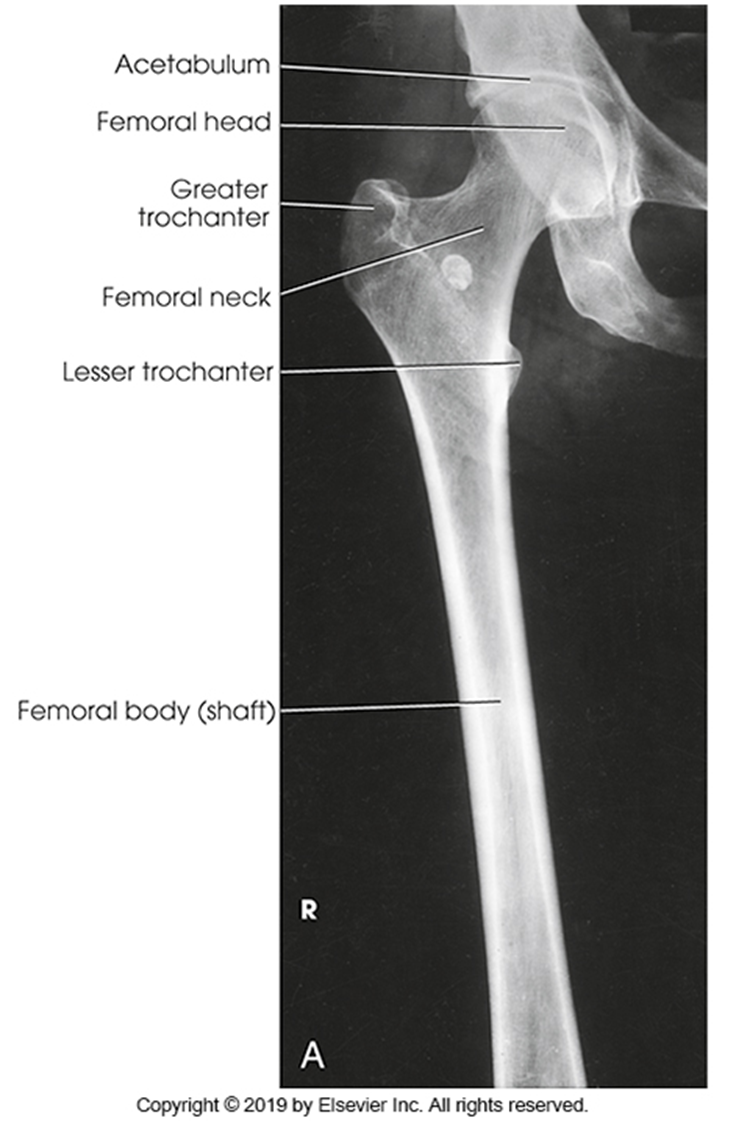

AP Femur

•Evidence of proper collimation and the presence of a side marker placed clear of the anatomy of interest

•Most of the femur and the joint nearest to the pathologic condition or site of injury (a second projection of the other joint is recommended)

•Femoral neck not foreshortened on the proximal femur

•Lesser trochanter not seen beyond the medial border of the femur or only a very small portion seen on the proximal femur

•No knee rotation on the distal femur

•Gonad shielding when indicated, but without the shield not covering proximal femur

•Any orthopedic appliance in its entirety

•Bony trabecular detail and surrounding soft tissues

Lesser trochanter is on, leg is not rotated in, under-rotated, hanging out too laterally

Leg was not internally rotated

No repeat, lesser trochanter can hardly see

Missing anatomy

slight medial rotation